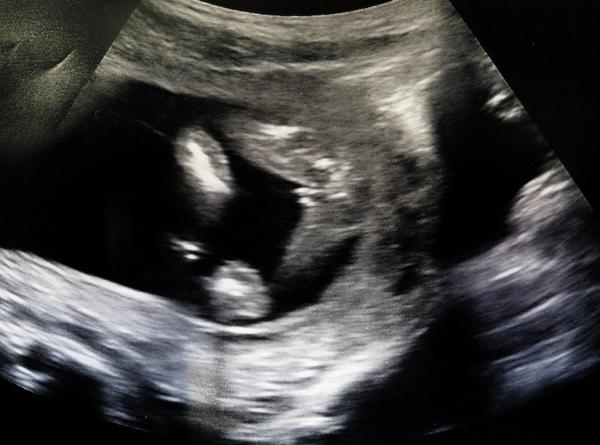

Ahoj maminky a budoucí maminky 😉 Prosím, poradila byste mi některá, co vidíte na fotce z ultrazvuku ve 20. týdnu za pohlaví? Určitě jste foteček viděly už mraky, proto vás žádám o radu...Nechci nikoho ovlivnit, proto svůj tip řeknu později 🙂 Děkuju moc!!!

No to já nevím 🙂 na příští týden jsem se objednala na lepší mašinu, utz u mojí doktorky je na houby a kór když se to přiblíží ☹ nepřikláněla se k ničemu konkrétnímu, že to může bejt teď ještě obojí (podle mě blbost, jenom ten ultrazvuk je na nic - mám doma už dvě děti, takže jsem pár utz u jiných doktorů už zažila) :-/